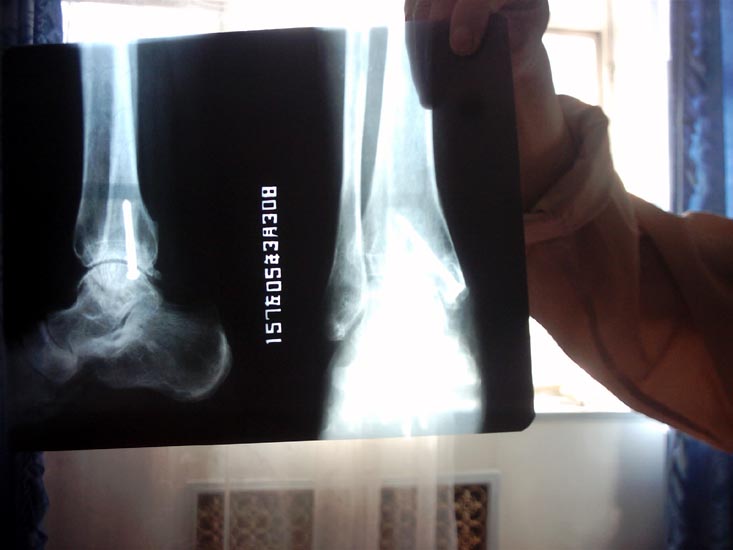

高精度图片高精度图片

骨折的X光照片

半个月过去了,我的小腿、脚越来越肿,队长们见事不妙。7月3日早9点多,连进财把我从劳动现场叫出来,由魏栋队长带着吸毒人员刘吉成和揽成宾开拖拉机把我送到厂部医院,拍了片子后,医生对魏队长说:“回去跟你们主管说一下,这个人再不能出工了。”然后给我的左脚打上了石膏,又拉回队里。当晚8点左右,全体人员在院子里开大会,我一个人在休息室。这时大队长邓德胜进来问我腿的情况,我如实作了回答,他对吸毒人员马成林交代:“不管谁问某某的腿,都不能说是打的(马成林事后告诉我的)。”然后马成林把我叫到教室,跪在地上求我:“别人问起千万别说是打的,我也没办法,是连大(连进财)叫我这么干的。”那几天,上厕所也不让人扶,让我单腿蹦。7月18日,见我的腿未见好转,又送到兰州大沙坪康泰劳改医院进行检查,确诊为左脚踝关节粉碎性骨折,大骨碎裂,并决定手术。

手术时,我听见医生们议论:“真是惨无人道,太卑鄙了,给人打成这样。”手术把我的脚关节骨盖摘除,大骨用螺丝钉固定(螺丝钉至今未取)。在我手术期间,他们为了封锁消息,把跟我一同送来一起迫害的同修叫到办公室问:“某某的腿那天晚上有人打了吗?”同修说:“吸毒人员打的。”又问:“值班队长不在吗?”同修说:“队长知道。”他们马上说:“队长不会这样做,以后不许胡说!”8月3日将我送回三大队,可马成林却不见了。有几个吸毒人员偷偷告诉我,队里怕事情败露,以调查为由,把马成林带走了,实际上是放了。后来我的亲戚来平安台向队长询问我腿的情况,队长却说是我自己绊的。我的亲戚说:“我如查出不是绊的,是你们打的,我就告你们。”后来连进财找我单独谈话:“某某,你的腿是马成林打的,是上面的意思,跟我可没关系,你出去千万别找我麻烦,我拖家带口也不容易啊!”此后,怕我告他,经常假意关心我。2004年平安台的法轮功修炼者都被集中到六大队十六中队,他们怕恶行败露,把我一人关到二楼十七中队,不准见太阳,吃饭也不让出去,让互监打进来吃。2004年5月又把我转到十八中队,始终封锁消息。我去要医院给我拍的片子,他们不给,我的家人也到康泰医院去要我的手术记录、片子,可医院告诉我家人,劳教所把片子、治疗记录全部取走了。2005年3月7日从劳教所解教回家后,我得知原工作单位解除了我的劳动合同。我到医院又拍了左踝关节正侧位片,片上螺丝钉清晰可见,确诊左踝仍有慢性创伤性关节炎。